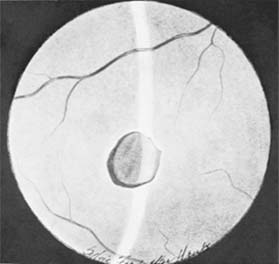

In addition to rupture of the scleral wall, contusive forces to the eyeball can result in motility disorders, subconjunctival hemorrhage, corneal edema, iritis, hyphema, angle-recession glaucoma, traumatic mydriasis, rupture of the iris sphincter, iridodialysis, paralysis of accommodation, lens dislocation, and cataract. Injuries sustained by posterior structures include vitreal and retinal hemorrhages, retinal edema (commotio retinae, or Berlin's edema), retinal holes, vitreous base avulsions, retinal detachment, choroidal rupture, and optic nerve contusion or avulsion (Figures 19-3 and 19-4).

Figure 19-3

Figure 19-3: Hole in retina, macular area, posttraumatic.

Figure 19-4

Figure 19-4: Choroidal ruptures. (Photo by Diane Beeston.)